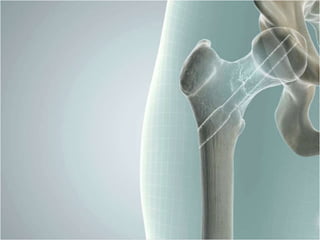

Expanding Bolt Osteosynthesis

for the Proximal Femur

Get your (femoral) head fixed right

•   60% larger frontal load area

•   Strong, secure fixation

•   Rotationally stable

•   One shot (centre-centre) fixation

•   Dynamic sliding compression

•   Reversible & removable

Perpendicular Expansion = No Disruption

Compacts bone = better stability